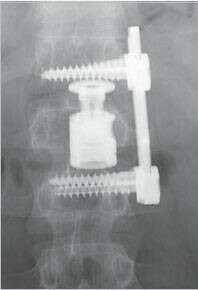

Всем привет. Хочу поделится своей историей. В 17 году у меня случилась производственная травма. Провалился пол. Летел метров 6 на арматуру. Хотя сам не строитель. Работаю АСУТП. Сломал спину-грудной отдел и две ноги. На левой пятка на пополам а правая нога раздробил стопу. Скорая увезла в больницу. Сделали две операции. В спину и в ноги поставили титановые пластины с болтами. Правую ногу ели собрали. Прошло время. А кстати дали третью рабочую группу и 40 процентов потери здоровья. На работе легкий труд. Ремонтирую и проверяю электронику. В этом году сделали снова операцию на спине. Был еще компрессионный перелом когда я получил производственную травму. Поставили кейдж систему. Это домкрат который разделяет и одновременно держит два позвонка. А что бы его установить надо старую конструкцию на спине расслабить, распороть живот. Удалить часть ребра. Так как установка ставится не со спины. И вывернуть все органы. Установить и снова зашить. Операция длилась 12 часов. В пятницу в 9 утра увезли в операционную. Но что то пошло не так. Очнулся только в субботу в 6 вечера. Врачи говорят была остановка сердца. Но я выжил. Сейчас даже незнаю что делать. Наверное дадут вторую группу. Эта история про то. Что наша жизнь такая хрупкая и не знаешь где упадешь. Случись в другом месте со мной а не в столице наверное врачи забили бы на меня. И организация помогла деньгами на операцию. Не бросила. Ниже несколько фото.